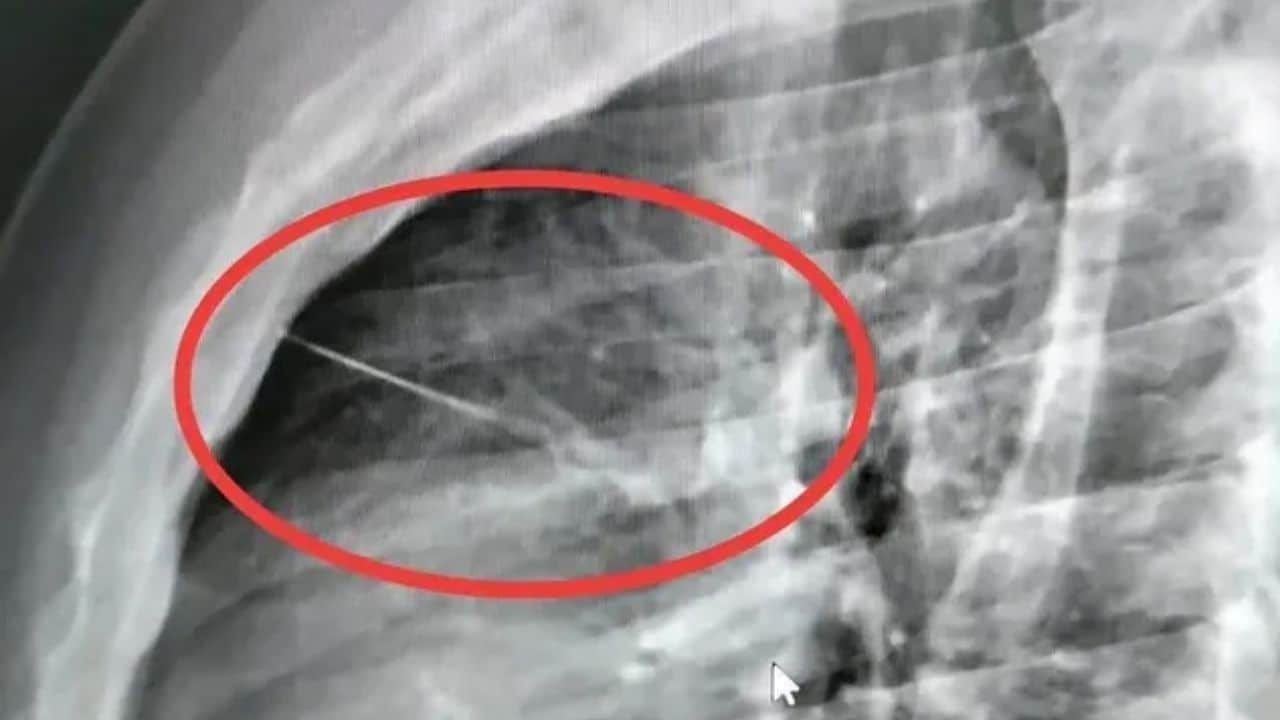

Man went to high-risk surgery after needle was found near his heart

A 27-year-old man in Thailand underwent high-risk surgery after a 7cm needle was found embedded in his chest, near his heart.

After an X-ray, hospital staff found that he had a small, sharp object lodged near his heart.

The object was later identified as a needle measuring about 7cm.

Source: Siamrath